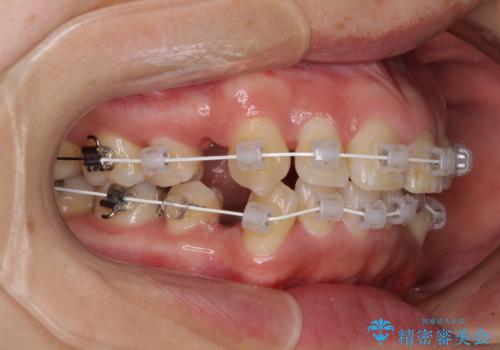

- 矯正装置

- 審美装置

- 1年8ヶ月

- 10-30回